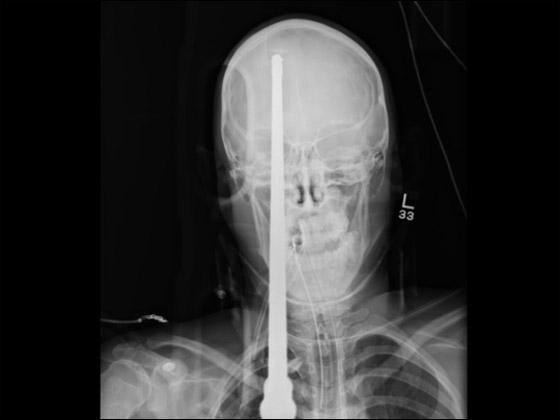

لعبت معجزة حقيقية دورها في نجاة مراهق أميركي من موت مؤكد، وذلك بعد أن اخترق رمح جمجمته. وأظهرت صور أشعة سينية كيف اخترق رمح الصيد رأس المراهق ياسر لوبيز (16 عاماً) الذي تعرض إلى ذلك الحادث خلال ممارسته هواية السباحة في بحيرة قريبة من بلدة ميامي- ديد التابعة لولاية فلوريدا.

ووفقاً لما أوردته صحيفة أميركية فإن الرمح الطائش انفلت من صياد أسماك بالخطأ وانطلق ليستقر في جبهة المراهق مخترقاً جزءاً من رأسه قبل أن يبرز جزء منه من الجانب الخلفي من الرأس. وقال الأطباء الذين أسعفوا المراهق المحظوظ انه نجا من الموت بأعجوبة، إذ ان الرمح لم يتسبب في تمزيق أي شرايين أو مراكز حيوية في المخ، منوهين إلى أن لوبيز يتعافى حاليا بشكل جيد ومبشر في مستشفى جاكسون ميموريال. ونقلت الصحيفة عن أحد الأطباء قوله: "انها معجزة حقيقية كون الرمح لم يمزق الأوعية الدموية الرئيسية في المخ"، مشيراً إلى ان عملية استخراج الرمح كانت صعبة جداً لكنها تكللت بالنجاح بعد 3 ساعات من الجهود الجراحية المتواصلة. لكن الأمر الذي يقلق الأطباء حالياً هو أن المراهق المصاب لا يستطيع أن يتذكر ما حصل، وهو ما ينذر بأنه ربما يكون قد أصيب بفقدان جزئي أو كلي للذاكرة.